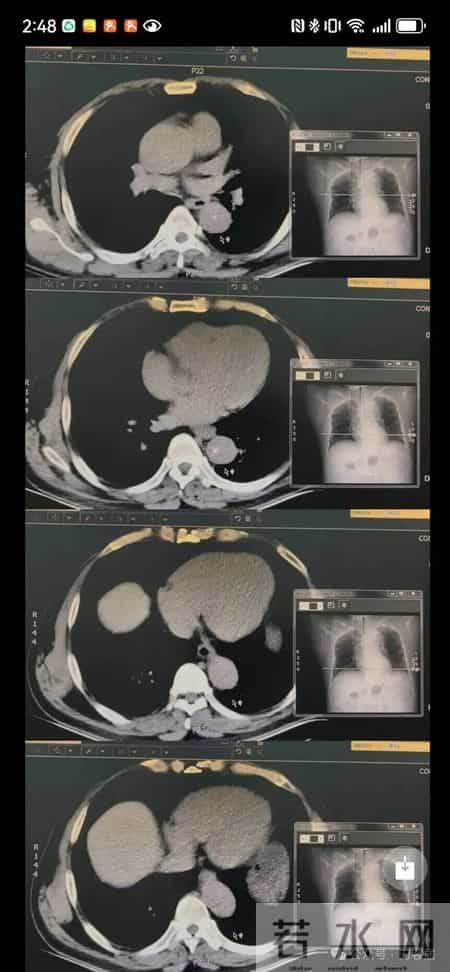

患者54岁男性,5年前口罩期间凌晨5点以“右下肢抽痛”之主诉急诊入院,有高血压病和腰椎间盘突出症病史,自觉椎间盘犯了要求住骨科,门诊筛查了胸部CT就办理入院,胸部CT是他唯一的检查,中午时病人猝死,报告单都还没出。病人的片子如下:

请问你通过这个CT片子考虑啥问题?

这张片子,说实话,我只看到了胸椎管未见明显的椎间盘突出及椎管狭窄,视野内肋骨未见骨折畸形。胸椎以外的组织中,我是没看到有其他异常的,也看不出胸椎以外的其他组织结构的病变。